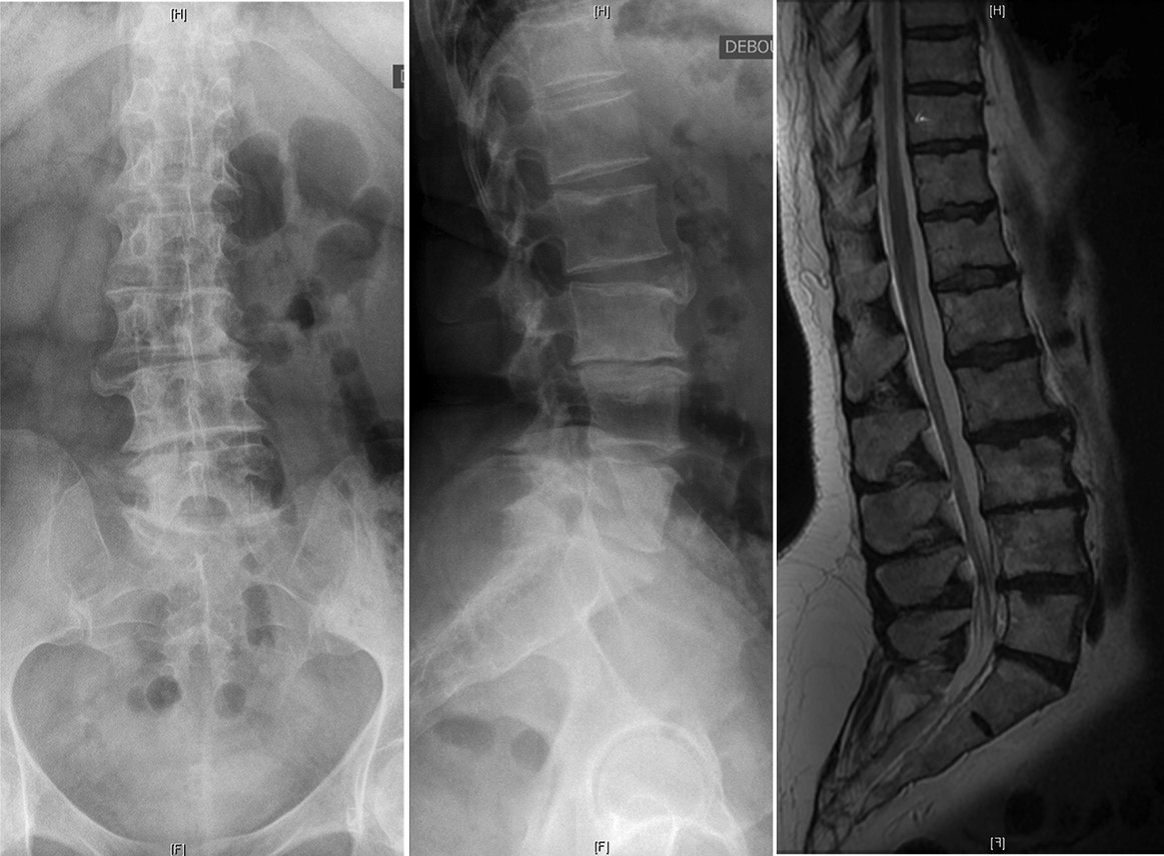

微创治疗占据一席之地

在过去的十年中,微创MIS技术治疗ASD已取得了重大进展。微创手术方式通常是通过前路腹膜后入路椎间融合器植入与后路经皮内固定相结合实现手术减压、固定及融合的目标。这种手术方式更适用于轻度到中度的ASD患者,此类患者多表现为有限节段的腰椎退行性改变和较好的弯曲柔韧性。对于MIS手术,单或双节段的退变为MIS治疗的良好手术指征,此时进行早期干预能够防止弯曲进一步的发展。目前已存在较多的文献表明通过MIS技术能够有效地矫正腰椎畸形,并且可以改善腰背痛以及神经根性疼痛。 Phan等对MIS技术治疗ASD患者进行荟萃分析后提出MIS技术的远期融合率满意且并发症发生率相对较低。Kanter等在其对MIS技术治疗ADS患者的综述中表明MIS技术在带来满意疗效的同时能够降低围手术期并发症。但是因其矫形能力有限,不建议将其应用于严重畸形的病例。

MIS技术通过结合后路经皮内固定和侧前路椎间融合器,使椎体获得重新排列,并对椎间孔狭窄进行间接减压。矢状面畸形矫正主要依靠前柱椎间隙的复位以及矢状面的腰椎前凸的恢复实现,即切除退变的椎间盘和前纵韧带以及椎间融合器的植入后节段性椎间隙高度的增加。而由椎体间隙不对称造成的冠状面畸形也可以通过椎间融合器的植入来矫正,从而使椎体终板重获平行矫正冠状面侧凸。椎间隙高度的增加与腰椎前凸的恢复使椎管与神经根管的骨性结构与软组织结构都实现了一定程度的撑开作用,从而对椎管狭窄起到了间接减压的作用。这种间接的前路减压技术可以解决开放性和封闭性半脱位,而无需对椎管进行侵入性操作。

腰椎L3-4椎间融合联合后路经皮椎弓根钉内固定。1年随访时CT显示椎间骨性融合

当然,MIS的局限性仍然是存在的。ISSG国际脊柱研究学组认为MIS技术仍然存在所谓的“天花板效应”以下情况不建议微创手术PI-LL > 20°,SVA > 9.5 cm,PT > 30°。严重的矢状面与冠状面畸形与失衡,僵硬性畸形或椎间已出现融合应通过后路开放手术解决。Mummaneni等将这一流程进行了细化,综合症状来源、冠状面和矢状面曲度、椎间盘退变程度因素将ADS分为6级。认定1-4级建议行微创手术,5-6级建议开放手术治疗。ISSG国际脊柱研究学组也曾提出基于影像特点的ADS患者手术方式的选择流程,并在2019年出版了最新修订的手术方式选择流程图。